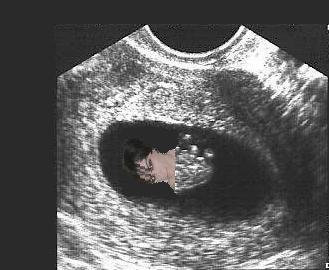

We had a little scare on Friday and I was given an early ultrasound. Fortunately, everything looked good. Baby measured just right for it's age (about 8wks) at 1.5cm and the little heart was beating along at a steady 145bpm (also very good). Everything else looked good as well. I thought I would include a picture for anyone interested.

baby2.jpg

baby2.jpg [ 19.12 KiB | Viewed 4237 times ]